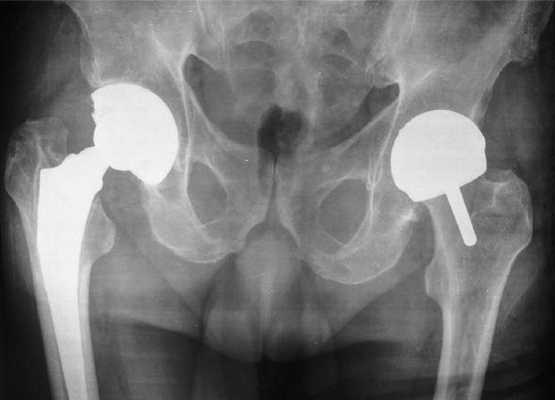

Интересный случай, двухсторонняя замена ТБС, но по разным технологиям. Слева тотальное протезирование, справа поверхностное.

Одновременное двустороннее эндопротезирование ТБС, рекомендуется в исключительно редких ситуациях, операционная травма будет больше, а, следовательно, и риск осложнений возрастет.